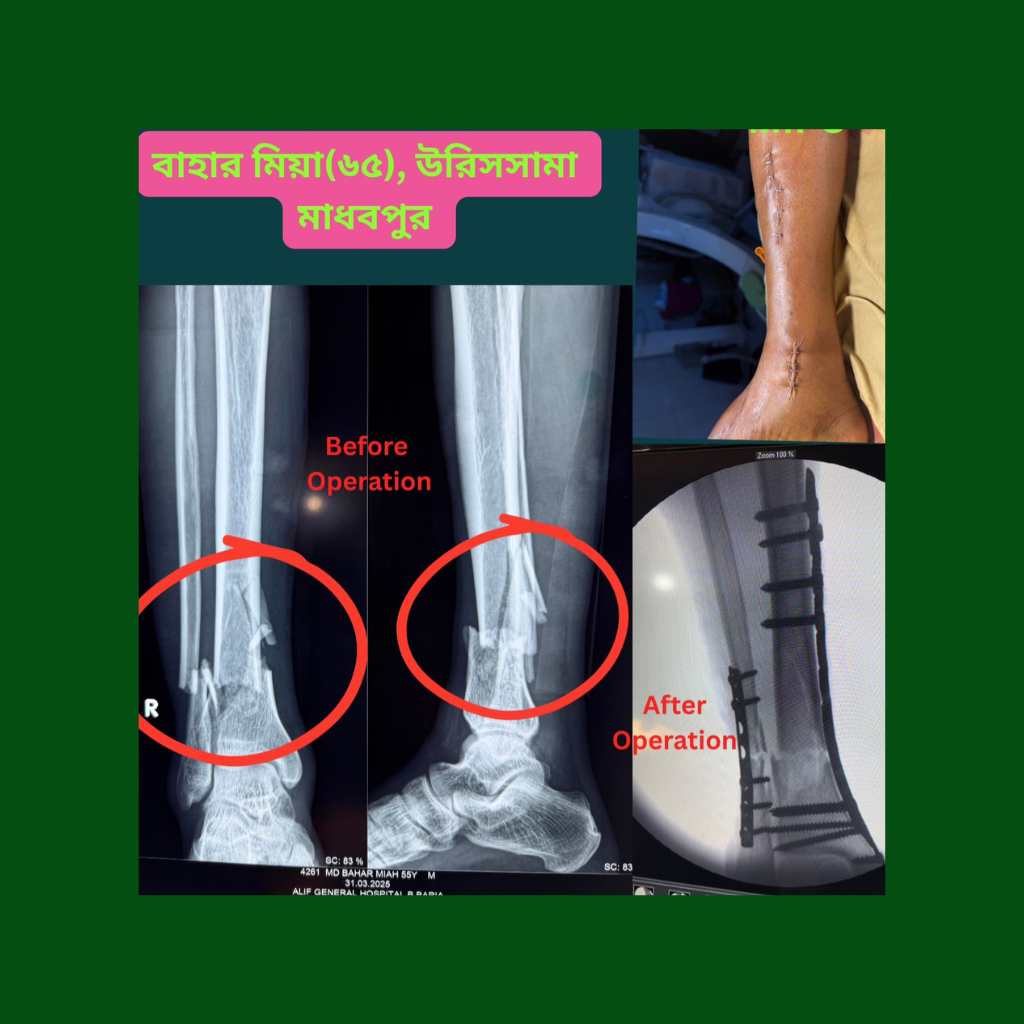

Ankle & Distal Radius Fractures

Anatomical reduction and internal fixation preserve joint congruity and minimize long-term degenerative changes following intra-articular injuries.